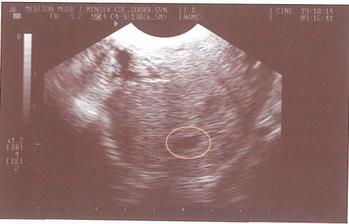

31.10.2008 první kontrola u doktora, potvrzeno těhu a dostali jsme fotečku s malou bublinkou